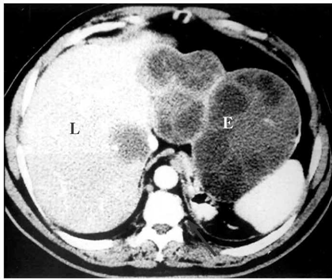

- בטומוגרפיה ממוחשבת ניתן לראות גוש בכבד עם כיסיות בנות, עם מחיצות או בלעדיהן (תצלום 12.10 - 13.10)